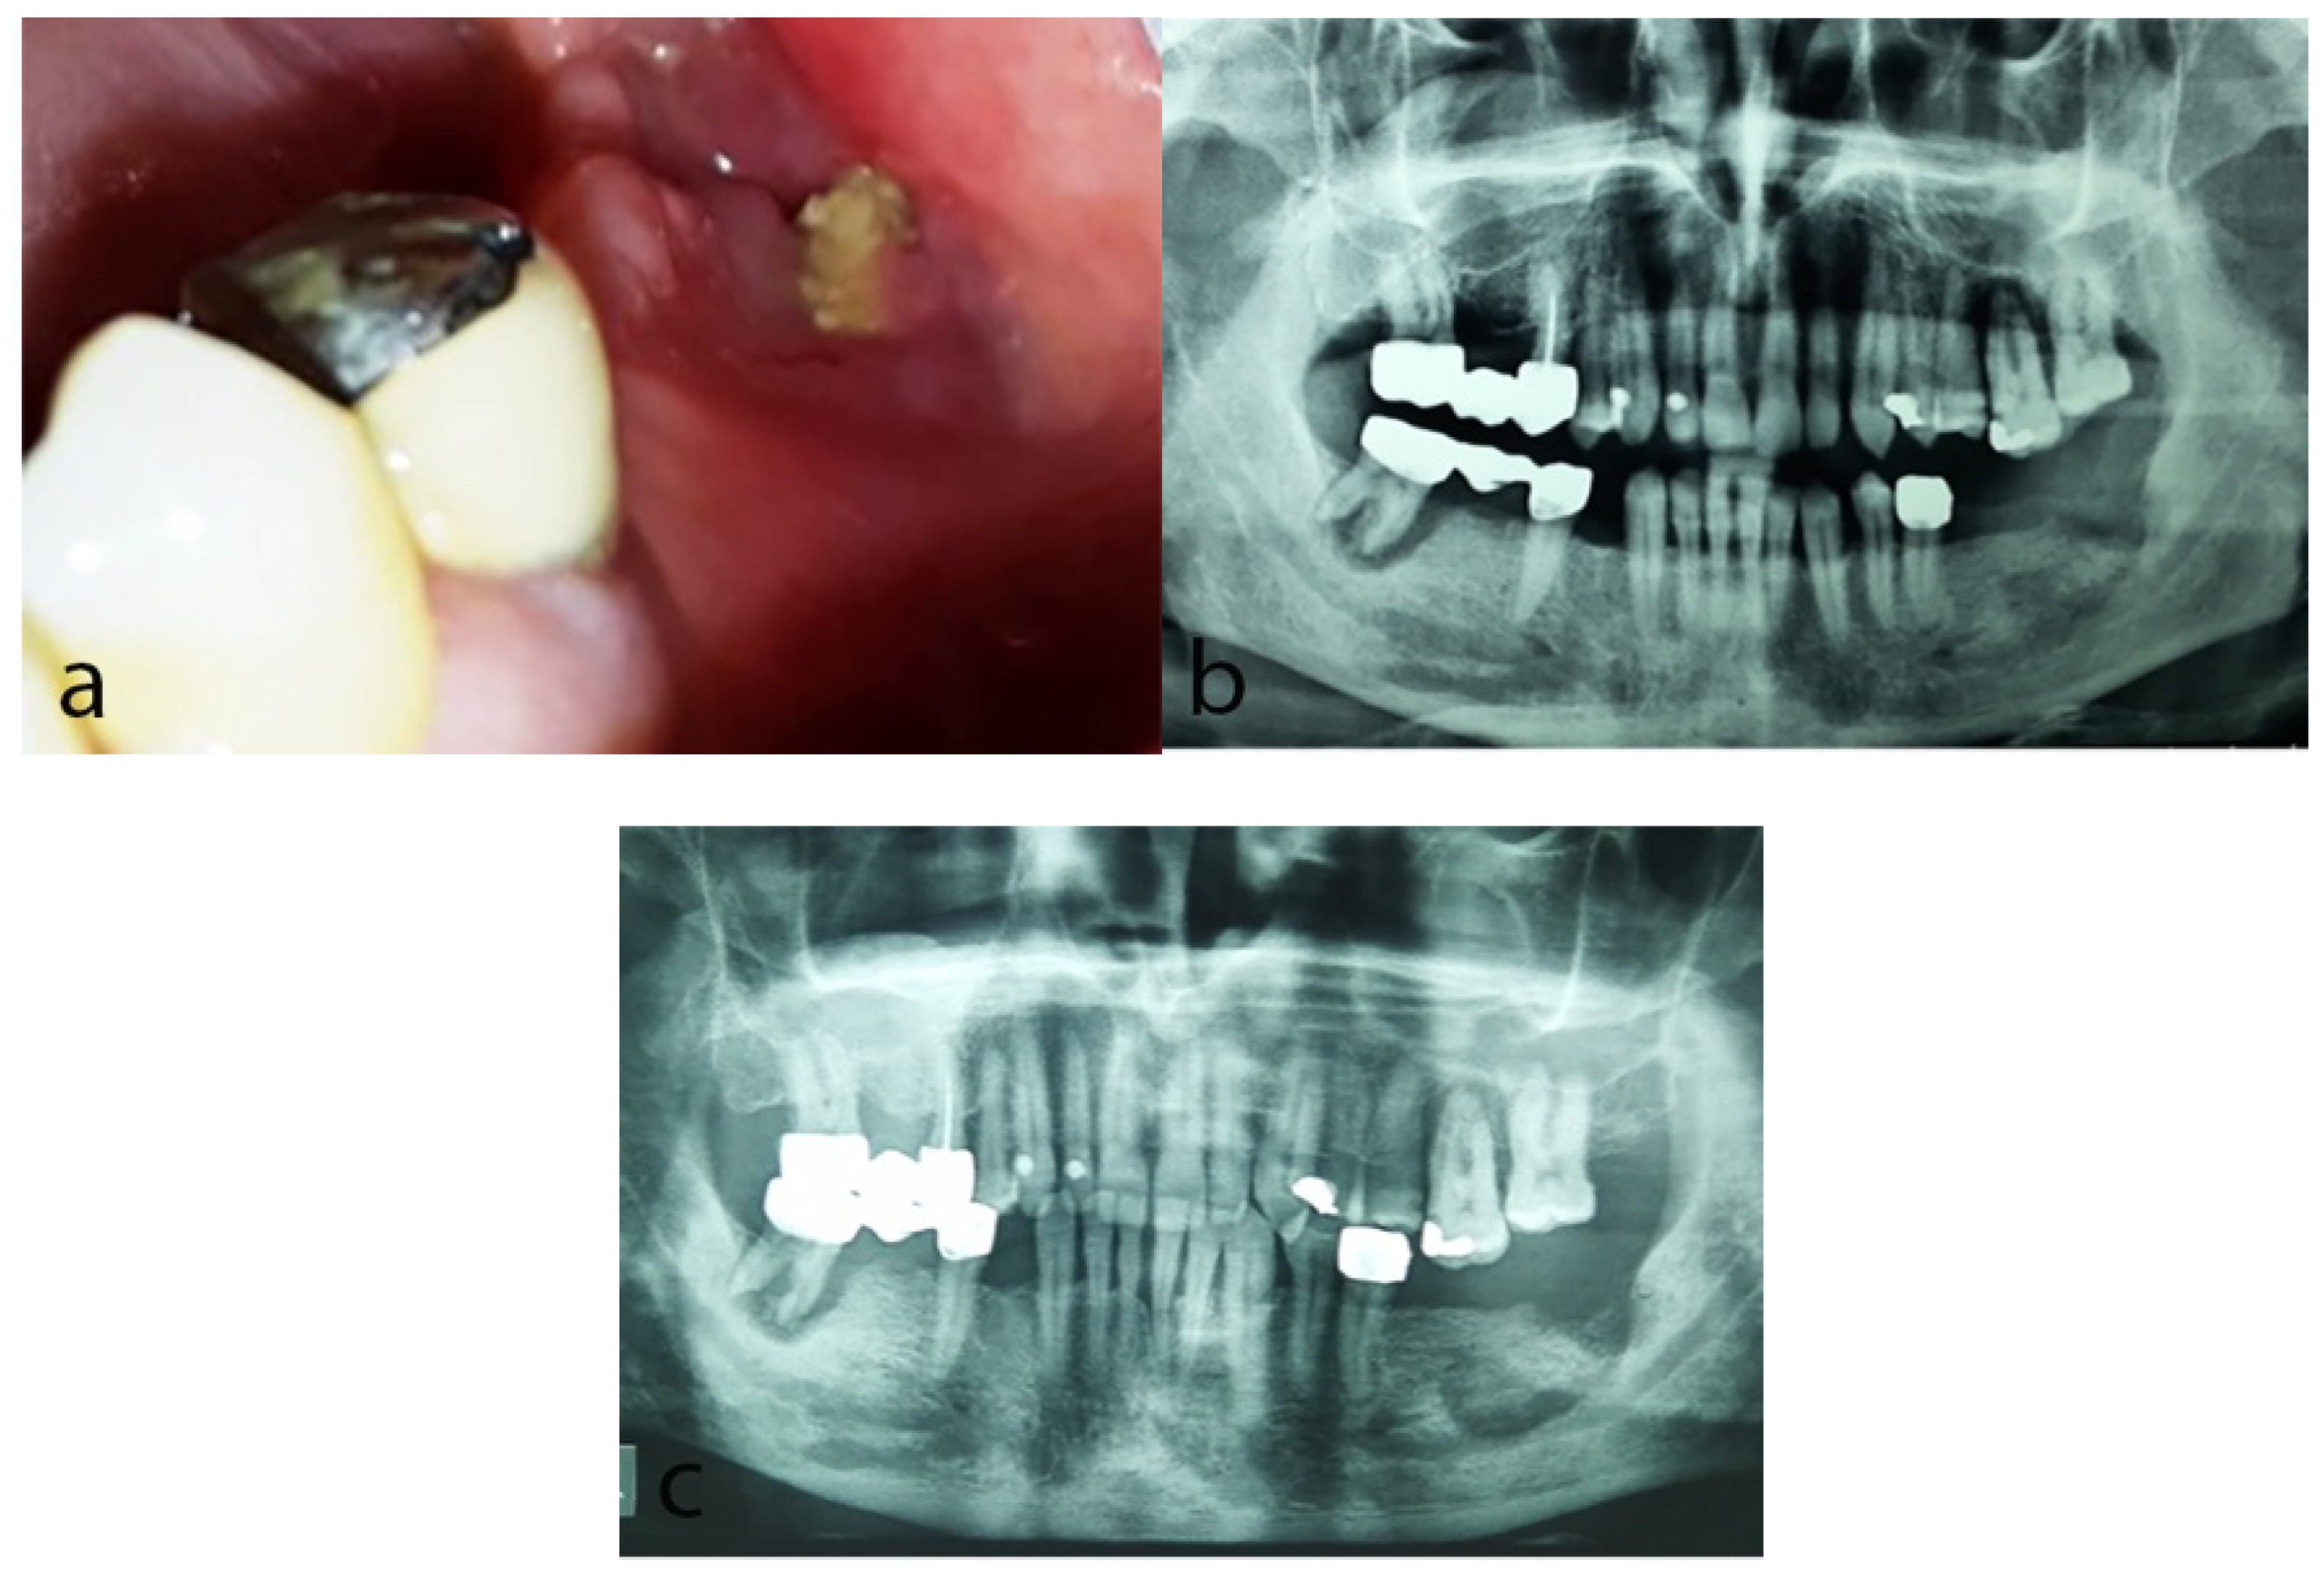

2.1. Case 1

2.2. Case 2